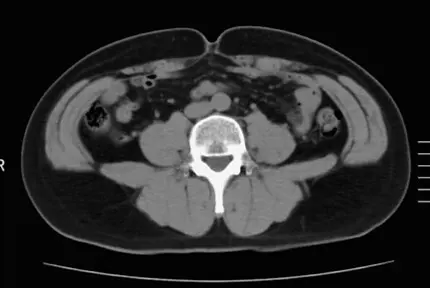

3週間で、体重−1.2kg、ウエスト−8cm!肝機能も改善した50代女性Aさん

BEFORE

体重 51.5kg

ウエストサイズ 78.0cm

体脂肪の量

全体 163.66㎠

内臓脂肪 39.55㎠

皮下脂肪 124.11㎠